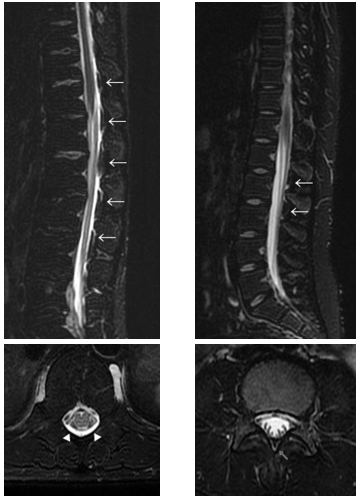

脊髄MRI(T2強調脂肪抑制像)

FDSS(矢印部)

左:頚椎部

右:下位胸椎部

(明舞中央病院症例)

(2)DTS (Dinosaur Tail Sign:恐竜のせびれ徴候)

(「画像診断」Vol.38 No.3 2018 脳脊髄液漏出症 P325-331 )

脊髄MRI(T2強調脂肪抑制矢状断)において、硬膜嚢背側の棘間部が弓状〜棘状の高信号を呈する場合がある。本所見は、横断像のFDSS〜iFDSSを矢状断として観察しているものであり、髄液漏出を示す所見と考えられる。

鹿戸先生(山形大学教授)

選定DTS(明舞中央病院症例例)

その他の代表例(明舞中央病院症例より)

DTS(←)とFDSS(▲)・iFDSS(⇧)↓